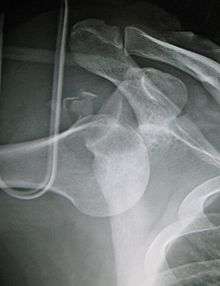

Inferior dislocation is the least likely, occurring in less than 1%. This condition is also called luxatio erecta because the arm appears to be permanently held upward or behind the head.[8] It is caused by a hyper abduction of the arm that forces the humeral head against the acromion. Such injuries have a high complication rate as many vascular, neurological, tendon, and ligament injuries are likely to occur from this mechanism of injury.